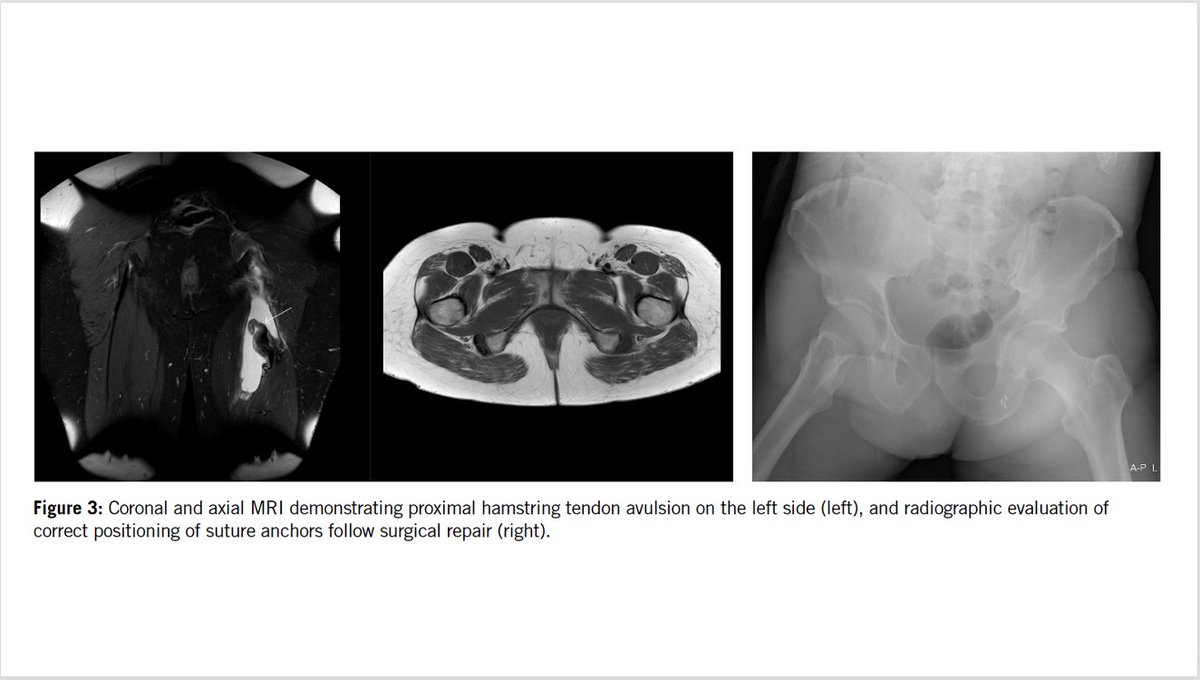

Do you like ice cream AND hamstrings? Use the ‘Dropped ice cream sign’ to identify proximal hamstring tendon avulsion on MRI: ▶️Tuberosity=Cone ▶️Tendons=Scoops, CaraMEl (Conjoint MEdial) & StracciatelLA (Semimembranosus LAteral) ✅Agreement: κ=0.87 🔓 https://t.co/sTdqORGTFt

#ParisOlympics 🗼 Management of Hamstring and Rectus Femoris Tendon Injury in Elite Track and Field Athletes There is little debate on the relevance of thigh muscle injury in elite sports. Their incidence, impact on athletic as well as team performance, and tendency to recur